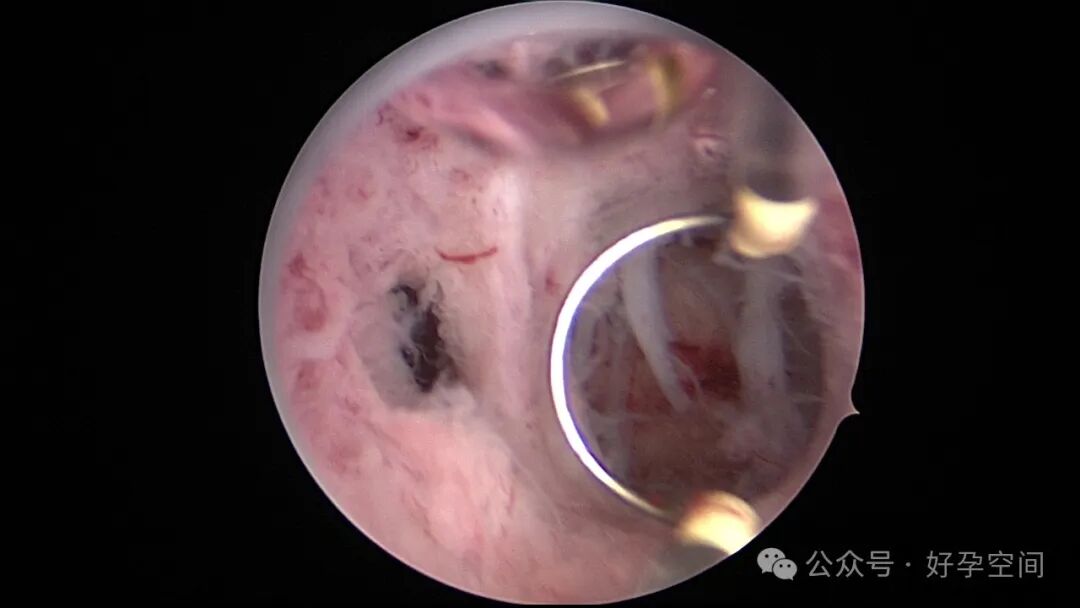

病例3:26岁,孕产史不详,本次停经60+天,稽留流产,宫腔镜辅助下清宫,见剖宫产瘢痕憩室,左侧宫角2.0cm*1.5cm组织凸起,难以清除,宫腔镜电切送病检,病检结果为蜕膜组织及平滑肌组织。

病例4:34岁,G3P1,顺产1次,本次停经40+天,计划外妊娠,宫腔镜辅助下清宫,宫腔前壁2.cm*1.0cm组织难以清除,家属拒绝切除送病检,术后2周复查B超,宫腔查见1.1cm*1.0cm占位,无血流信号,门诊随访。